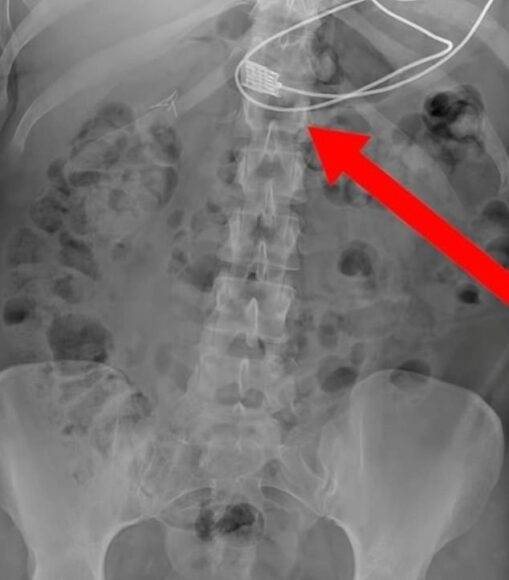

14일(현지시간) 과학 전문 매체 라이브 사이언스 등에 따르면 미국 웨인 주립대(WSU) 의과대학 연구진은 최근 ‘정신의학 사례 보고서’에 이같은 진단 사례를 공개하고 “철 결핍이 아닌 비타민 결핍 환자에게서 이식증(異食症)이 나타난 첫 번째 보고 사례”라고 밝혔다.

보고서에 따르면 미국 미시간주에 사는 여성 A(36)씨는 극심한 호흡 곤란과 빈혈, 복통, 피로 등을 호소하며 병원을 찾았다. A씨는 비만과 수면 무호흡증, 비타민 결핍 등 여러 질환 및 증상과 불안, 우울증, 외상 후 스트레스 장애(PTSD) 등을 앓고 있었다.

의료진은 A씨가 극심한 비타민 B12 결핍을 겪고 있다는 것을 발견했으며, 추가 검사를 통해 A씨가 비타민 B12의 흡수를 방해하는 항체를 가지고 있다고 진단했다.

철분 부족으로 발생한 철결핍성 빈혈이 있는 경우 이식증이 나타날 수 있다. 그러나 이 여성의 경우 철분 결핍은 없었으며, 비타민B12 결핍으로 인한 빈혈이 이식증으로 이어진 이례적인 사례라고 보고서는 설명했다.